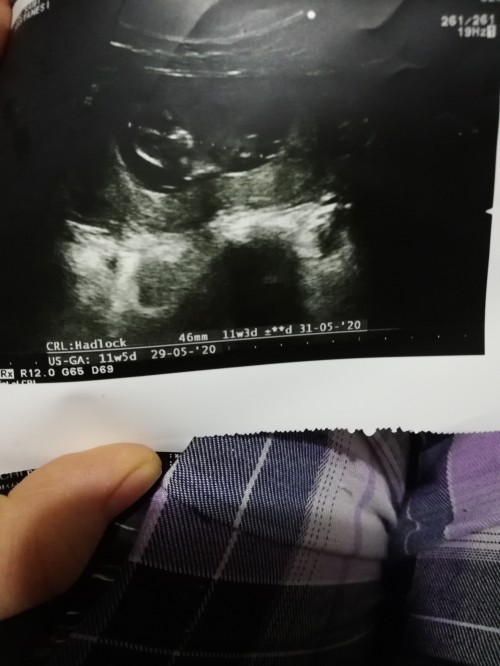

image12 haftalıkken canım olursa? bi de bilgileri yazmıyo burda o haftadaki gelişim bilgilerini istersen yazabilirim. sorun ne hayırdır?

image

canım biraz geç oldu kusuruma bakma gündüz misafirim vardı cok telaşlıydım şimdi atabildim, sadece bunlar yazıyor baska bilgi yok